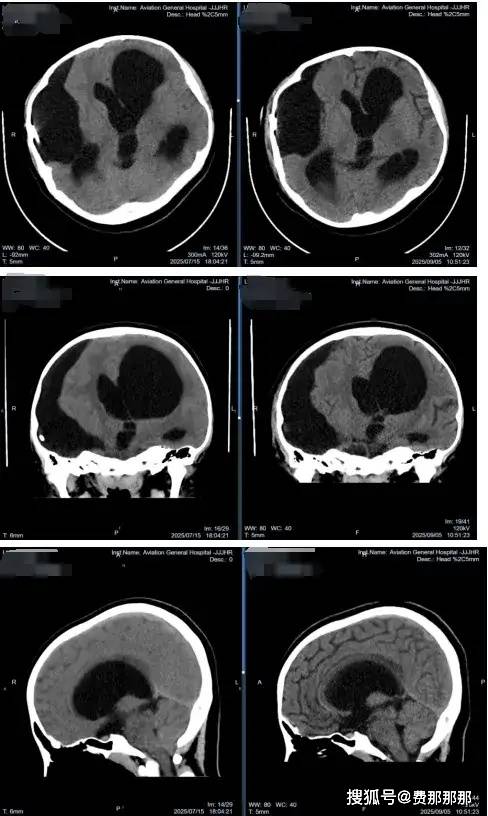

2025年7月,13岁的小廖因“进行性加重性行走障碍,左侧足外翻,右侧肢体活动不利、抖动”找到北京航空总医院肖庆主任。这本应享受校园生活的年纪,她却已经在病痛折磨中度过了十年之久:3岁时发现右颞蛛网膜囊肿,当地医院行开颅囊肿剥离手术;4岁时囊肿复发增大,又行囊肿-腹腔分流术;9岁时出现分流管感染,不得不行分流管拔除术并植入囊肿储液囊(Ommaya囊)……随后多年,虽然经历了多次手术和抗感染治疗,小廖的病情仍然逐渐加重——脑室系统扩张、右颞囊肿张力不断增加、中线结构移位明显。这不仅影响了她的运动功能(行走障碍、肢体活动不利),也影响了她的生活技能和认知发展。

一期清创:利用软性内镜的灵活性和广视野,一期手术同时完成感染装置取出、脑室系统探查与灌洗。术中,肖庆主任凭借精湛的技术和丰富的经验,通过神经内镜精准探查囊肿腔,发现原囊肿造瘘与脑室颞角贯通,颞角脉络丛稍苍白。随后,团队成功拔除原分流管,将腹腔端分流管连接至脑室引流管,确保引流通畅。术后,脑脊液NGS检查发现腐生葡萄球菌、表皮葡萄球菌感染,这也印证了肖庆主任在门诊的第一判断,团队立即给予万古霉素抗炎治疗,监测脑脊液逐步改善,直至各项指标均达到合格。

二期重建:待感染控制后,及时实施ETV等脑脊液循环通路重建手术,这是避免再次置管、获得长期良好疗效的保障。术中,肖庆主任通过内镜进入脑室,发现脑室壁内欠光滑,透明隔破溃,室间孔向左侧扭曲变形。在三脑室底,团队以双腔球囊穿刺扩张瘘口直径至6mm,松解基底池粘连,并冲洗脑室。